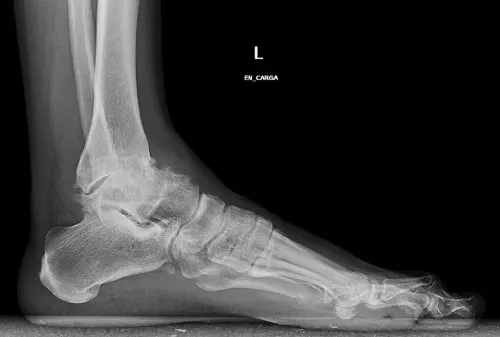

Cómo se origina la artrosis de tobillo

Este tipo de artrosis se origina por el desgaste progresivo del cartílago de la articulación del tobillo.

- Es común que, al cabo de los años, el tobillo muestre tanto rigidez como deformaciones.

- También pueden aparecer los clásicos espolones óseos. Estos hacen que sea una afección muy dolorosa, además de limitante.

Los traumatólogos también nos hablan de una causa muy peculiar: la propia deformidad del tobillo.

- En ocasiones, solo con tener los pies planos ya somos más proclives a desarrollar con el tiempo una artrosis del tobillo.